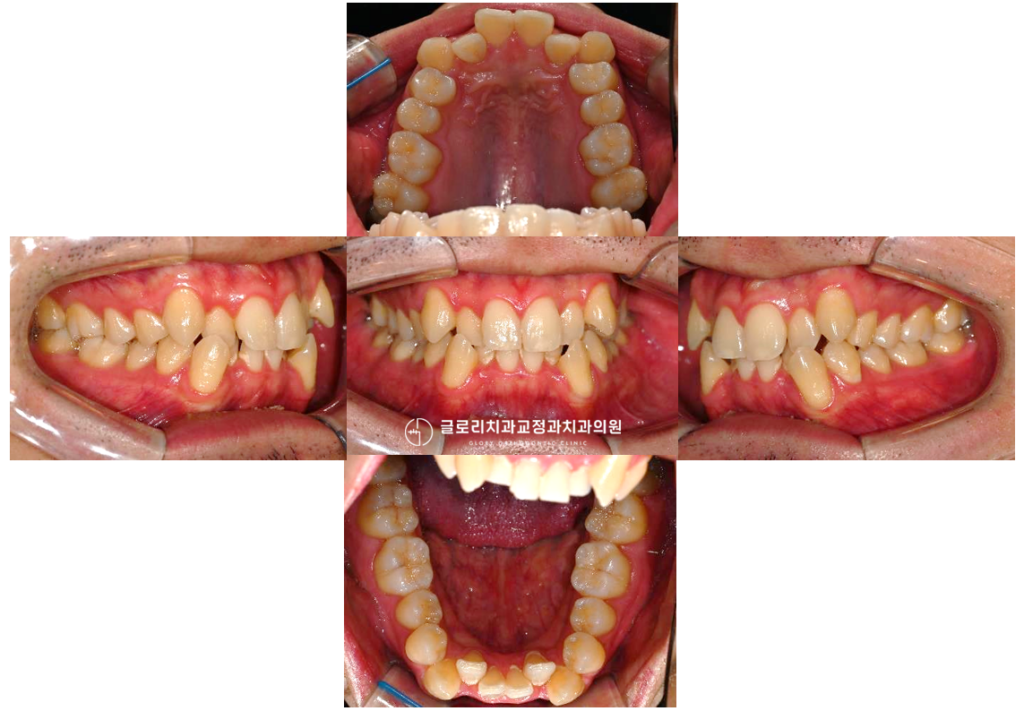

다음과 같이 치아가 겹쳐 있거나 틀어져 있으면 가지런한 치열을 가진 분들에 비해 일상적인 구강 관리에 어려움이 생깁니다.

또한 치열이 고르지 않으면 위아래 치아가 제대로 맞물리지 않는 경우가 많습니다.

이를 부정교합이라고 하며 음식을 씹는 기능에 직접적인 영향을 줍니다.

발치교정이 마무리되면 가장 먼저 느끼는 것은 치열이 가지런해진 외관상의 변화입니다.

겹쳐 있거나 튀어나왔던 치아들이 자연스러운 곡선을 그리며 배열됩니다.